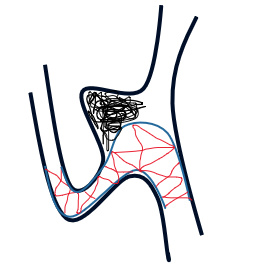

治疗策略

患者动脉瘤瘤颈累及M2段上干支和下干支;瘤体欠规则,患者既往行颅内动脉瘤介入栓塞治疗。

对于大脑中动脉分叉部动脉瘤,其位置相对表浅,在治疗时,可选择开颅夹闭或介入治疗;

动脉瘤所累及分支血管几乎自瘤壁发出,根据《2021年未破裂动脉瘤诊疗指南》,优选开颅夹闭;

但由于患者高龄,长期服用抗血小板药物,且患者自身选择介入手术意愿强烈,遂遵循患者意愿选择介入治疗。

瘤颈较宽,均匀累及双侧分支,计划选择金属覆盖率高的编织型支架,单一支架缩窄瘤颈,辅助弹簧圈栓塞(如下图);

能更好保护瘤颈和重建血管,起到一定血流导向的作用,达到远期治愈目的。由于瘤颈较宽,备“T形”支架技术辅助栓塞。